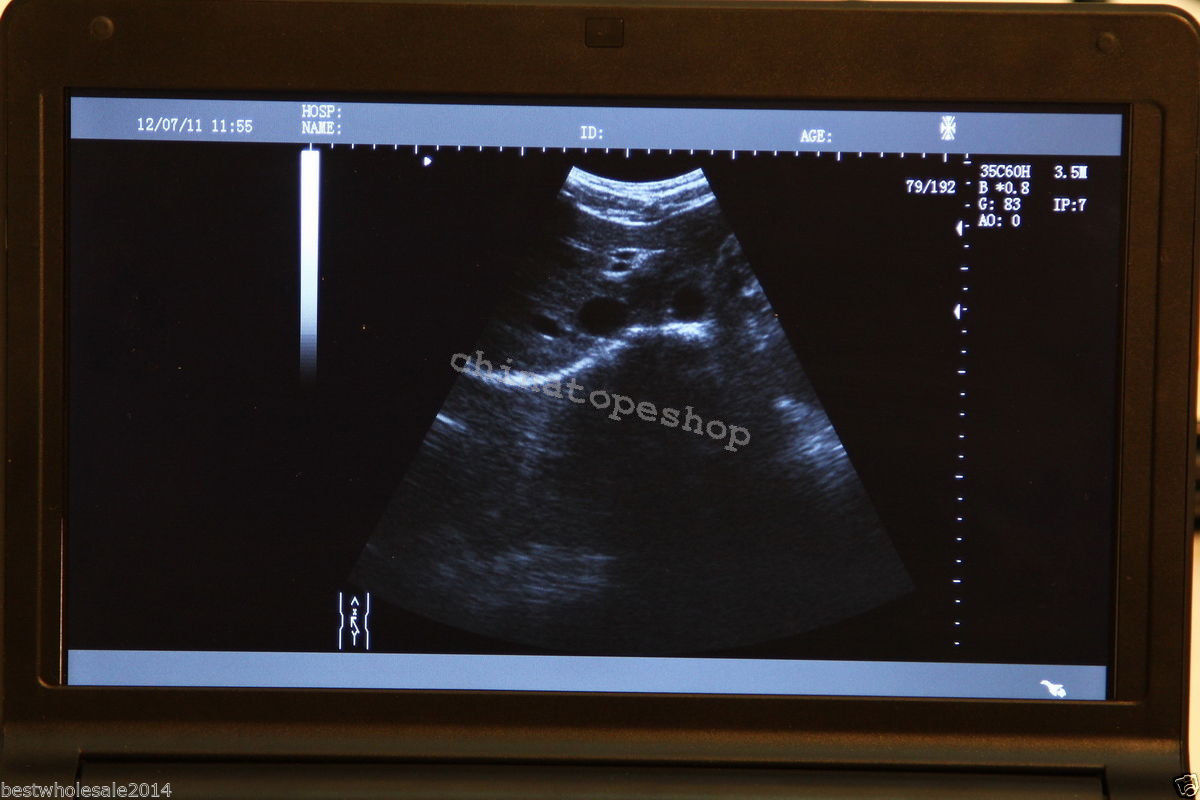

The Laptop Ultrasound Scanner combines cutting-edge technology with portability to enhance your medical practice. This device allows for high-quality ultrasound imaging, ensuring that healthcare professionals can provide accurate diagnoses. Additionally, it features a Transvaginal probe that delivers detailed views of internal structures, making it indispensable for gynecological examinations. Because of its sophisticated design, you can easily operate it in various clinical settings.

High-Quality Imaging Meets Practical Functionality

With the inclusion of a 3D workstation, the Laptop Ultrasound Scanner offers enhanced imaging capabilities that allow healthcare professionals to view detailed 3D images. This functionality improves diagnostic accuracy and helps in monitoring various conditions over time. Additionally, the software included enables efficient storage and easy retrieval of images, supporting medical professionals in their evaluations. Hence, this scanner not only provides high-quality imaging but also practical functionalities that are essential for modern medical practices.